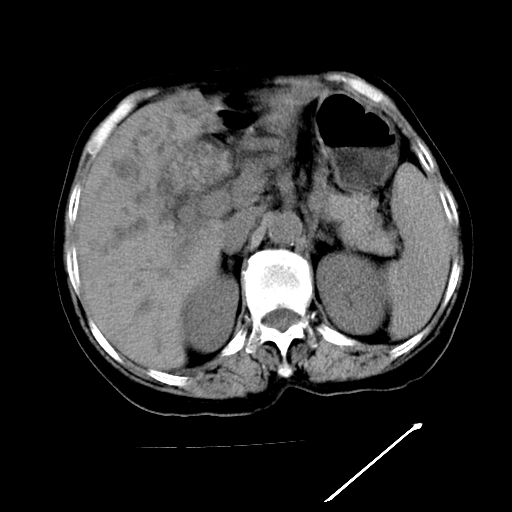

以下是引用随光逐影在2009-4-7 8:21:00的发言:[br]肝内外胆管多发性结石并肝内外胆管扩张;胆系感染。